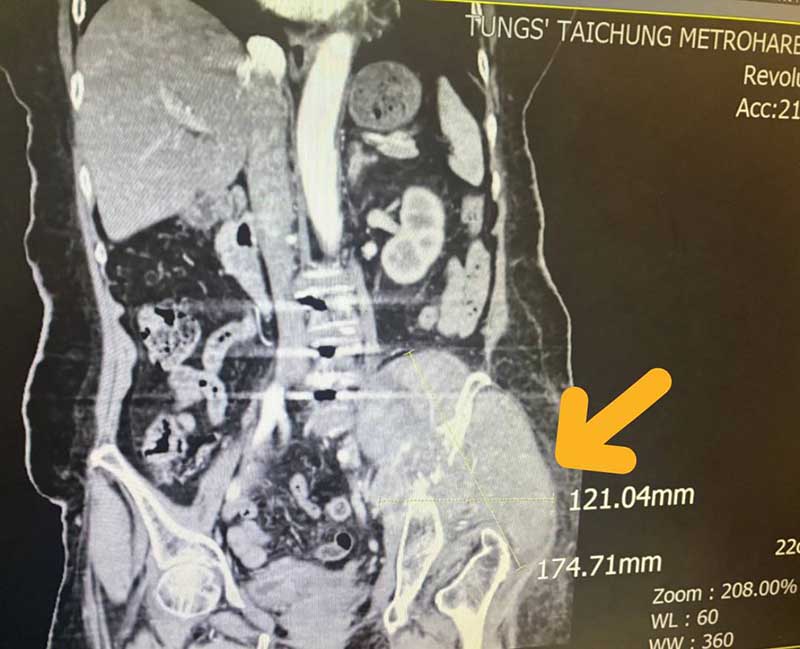

因腫瘤細胞太大(12.1公分x17.4公分左右),並且腫瘤位置執行手術風險過高,轉由放射腫瘤科葉啟源主任進行銳視刀適應性放射治療,利用空間分割點狀治療方式(Spatially Fractionated Radiation Therapy, SFRT) 在局部的位置給予點狀高劑量的放射線,再配合傳統銳視刀治療方式,經過一個月26次治療後,腫瘤已經縮小至9.8公分x10.1公分左右,縮小腫瘤後也讓疼痛獲得明顯改善。

黃色箭頭即為患者左側骨盆骶骨處出現異常12.1公分x17.4公分左右大型腫瘤細胞